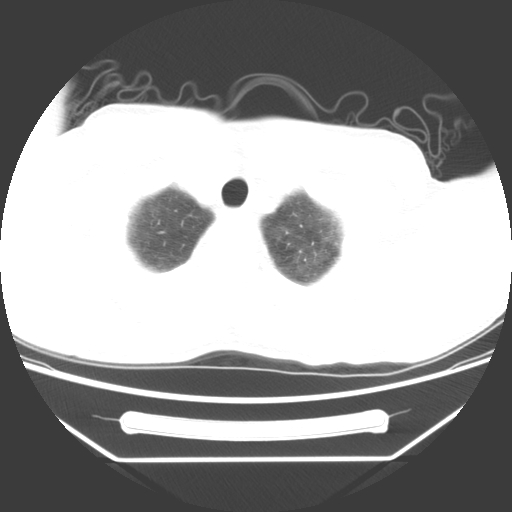

病人55岁,咳嗽,胸闷

忘了传病史了,病人55岁,咳嗽,胸闷

两肺部呈“毛玻璃”状改变,原因待查考虑感染性病变

病人是否发烧,两肺“磨玻璃”影,其间见空气支气管征和碎路石征。考虑肺泡蛋白沉着症。

两肺广泛对称磨玻璃样影,密度不均,考虑机遇性肺部感染。

双肺弥漫磨玻璃样病变,病史很重要。有感冒或发烧史,甲流不除外。无发烧可考虑肺泡蛋白沉积,但肺泡蛋白沉积边缘往往较清晰,与正常肺组织分界清晰

两肺弥漫间质性病变,考虑肺泡蛋白沉着症。建议进一步检查。

两肺“磨玻璃”影,其间见空气支气管征和碎路石征。考虑肺泡蛋白沉着症。

两肺部呈“毛玻璃”状改变,支持肺泡蛋白沉着症。